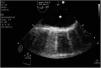

Paciente que ingresa en el hospital por síndrome coronario agudo complicado con comunicación interventricular (CIV). En un inicio se realiza tratamiento con angioplastia primaria y corrección quirúrgica de CIV. Durante el procedimiento desarrolló shock cardiogénico, con necesidad de balón de contrapulsación intraaórtico y ECMO-VA. A pesar del tratamiento hubo persistencia de CIV, por lo que se propone para trasplante cardiaco en centro de referencia. Previo a ello, se realiza angioTC con imagen compatible con disección de aorta ascendente (figs. 1 y 2), por lo que se desestima. Tras la revisión de imágenes en el centro trasplantador, se descarta disección tras valoración en ecocardiografía transesofágica del arco aórtico (fig. 3), considerando que la imagen se produce por confluencia de flujos de ECMO, lo que permite el trasplante.